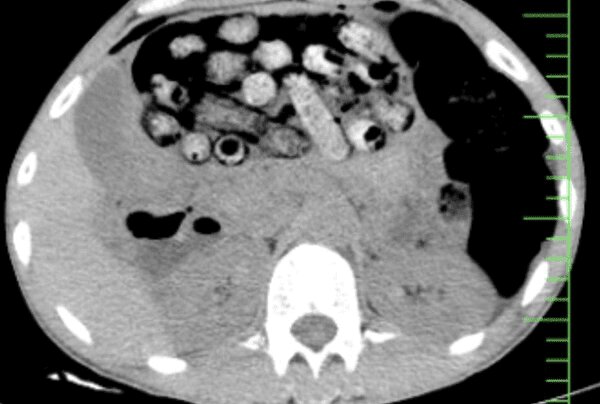

Univerza za medicinske znanosti Alborz je v mestu Karadž v Iranu sporočila, da so iz želodca in črevesja pacienta kirurško odstranili 90 paketov prepovedane droge.